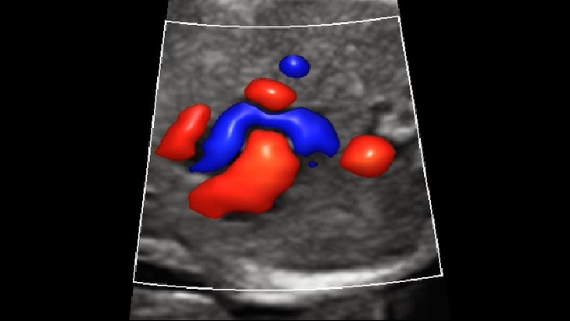

Imagens clĂnicas